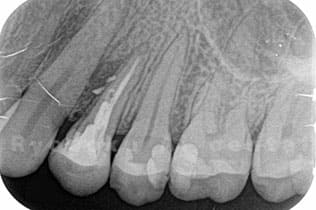

STEP 2

- レントゲン検査

- レントゲン写真にて、問題となっている歯牙の状態を確認します。

根の治療にて治る見込みがない場合や歯が割れている場合は抜歯となります。 -